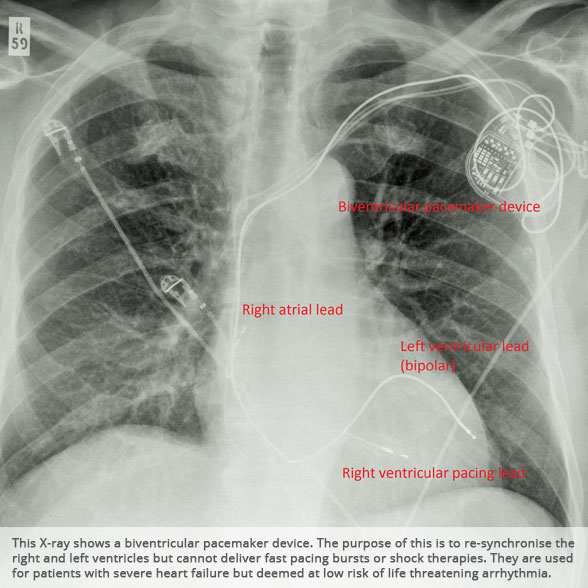

Biventricular pacemaker device Biventricular pacemaker device

BI-VENTRICULAR PACEMAKERS

Bi-ventricular pacemakers are used for the treatment of suitable patients with heart failure who are already on medication but who suffer from a lack of synchrony between the right and left ventricular contraction. This is most commonly caused by an electrical delay (left bundle branch block LBBB) in transmission of signals to the main pumping chamber (called the left ventricle) and is relatively common in patients with advanced heart failure. This delay process commonly worsens the symptoms of heart failure and it is not generally influenced by medication alone.

Although not all patients universally respond to bi-ventricular pacing (or cardiac resynchronisation therapy/CRT), patients with more advanced dys-synchrony tend to experience remarkable improvement. Bi-ventricular ICDs have the additional benefit of recognising life threatening arrhythmia and deliver both fast pacing bursts or shocks to restore normal heart rhythm.